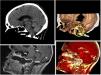

The brain computed tomography scan revealed clivus perforation (white arrow). The magnetic resonance imaging scan in turn also evidenced involvement of the odontoid process (yellow circle and arrow), consistent with regular cocaine use, with an associated abscess that compressed the pons and bulb of the mesencephalon.

Cocaine is known to cause destruction due to vasoconstriction and necrosis of the nasal septum and hard palate, but its effects on the skull base and even the cervical vertebras have been less widely described (Fig. 1).